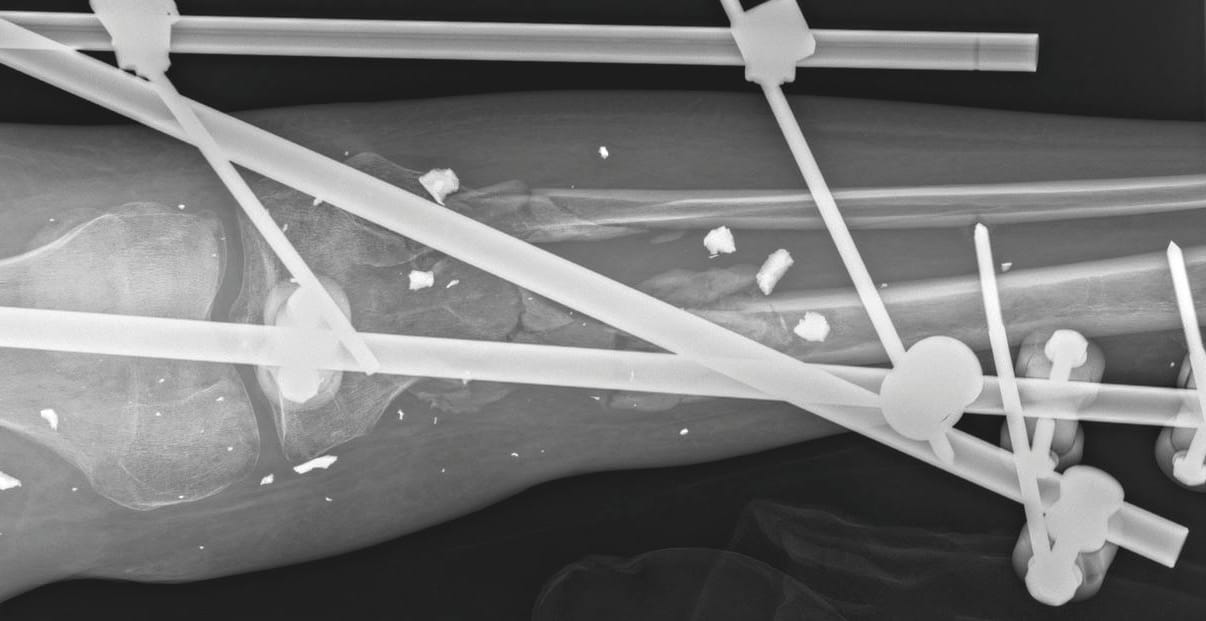

To better visualise the value of these examinations, please refer to Figures 1 to 3. Figure 1 shows a photo of a patient. It shows multiple injuries to the lower extremities with many small, seemingly non-irritant wounds and treatment with an external fixator. Figure 2 shows the corresponding radiograph of the right lower leg with the knee joint. Multiple small radiopaque foreign bodies can be seen. Figure 3 shows the evaluation using anti-granulocyte antibody SPECT/CT. It is very easy to recognize which foreign bodies accumulate granulocytes in their surroundings. This corresponds to an infection. Many other foreign bodies do not have this accumulation and are therefore not infected.

In an animal experiment with small, injected fragments, the authors were hardly able to find any relevant changes on the skin surface in many cases [2] Bowyer GW, Cooper GJ, Rice P (1995) Management of small fragment wounds in war: current research. Ann R Coll Surg Engl 77:131-134. This is consistent with our experience that, particularly in the case of blast injuries, the skin over the blasted foreign bodies often shows no evidence of infection. In order to clarify the question of which injuries we should treat surgically first, imaging - especially nuclear medicine imaging - was of great value to us. Even though the initial screening and the first debridements gave us a good picture of the extent of the infections and the infected regions at an early stage, this imaging repeatedly gave us indications of unknown centres of infection or possible reservoirs for germs in avital bone areas.